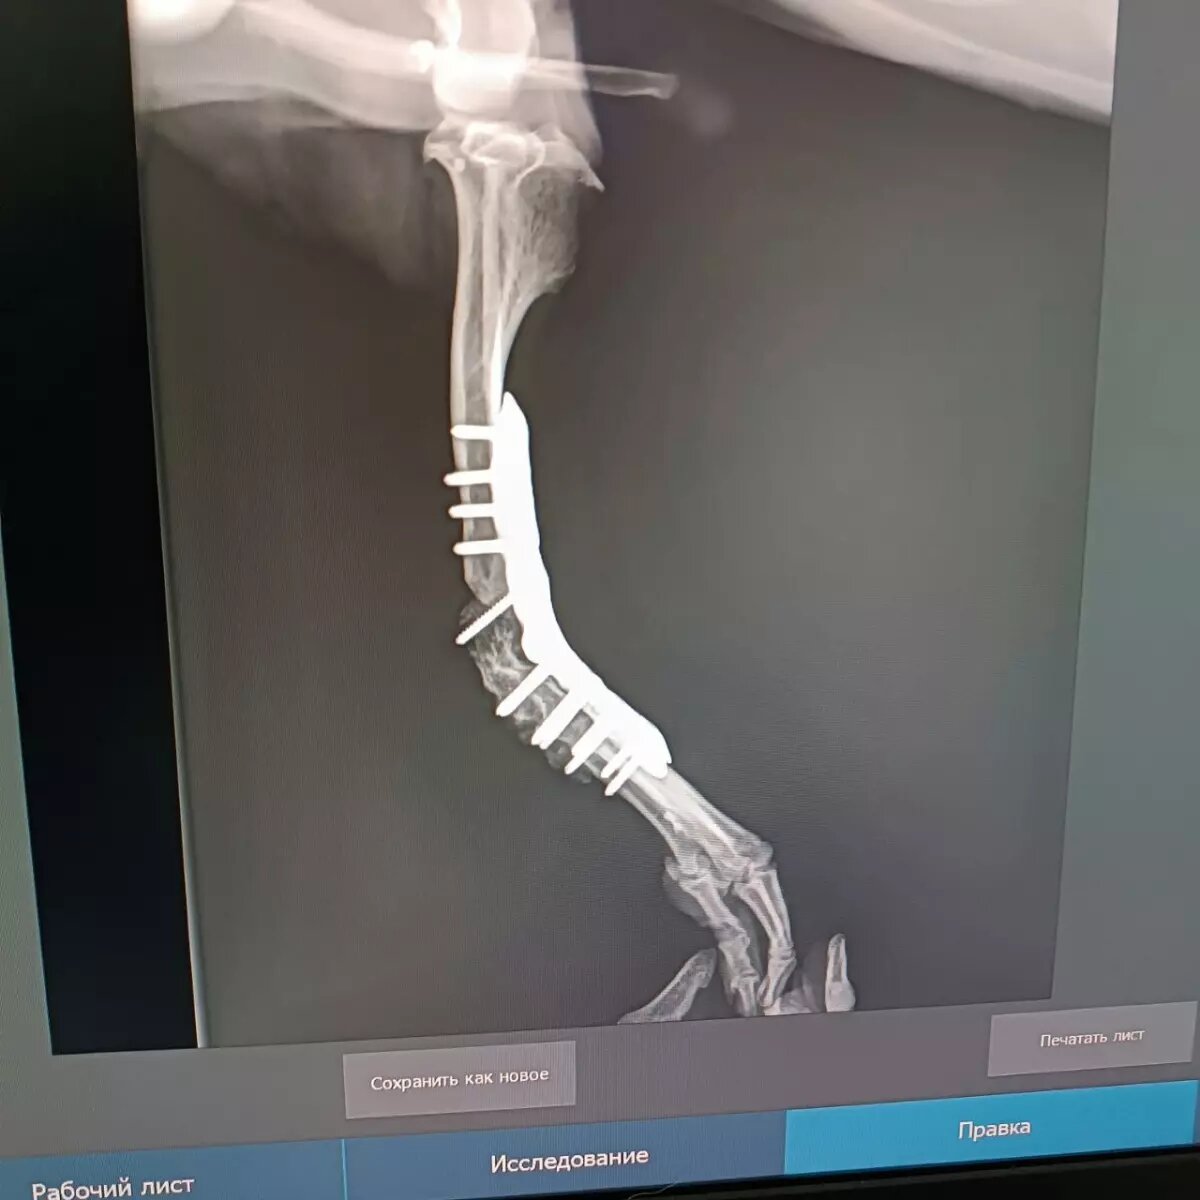

В конце октября Мите установили пластину в лапку. Несмотря на успешность операции, существовала высокая вероятность инфекции. Полная картина по итогам операции стала понятна спустя месяц.

- Сделали рентген, с пластиной всё хорошо, - рассказывает Юлия. - С каким мы нетерпением ждали результат об инфекции - всё хорошо, инфекции нет.

Однако срастания пластины с костями пока нет. Врачи сообщают, что это нормально — прошел всего лишь месяц. Чувствительность в лапке уже есть, но пес так и не опирается на нее. Кроме того, Мите нужна дорогостоящая операция на коленных чашечках и курс реабилитации. Стоимость только одной операции - порядка 140 тысяч рублей.